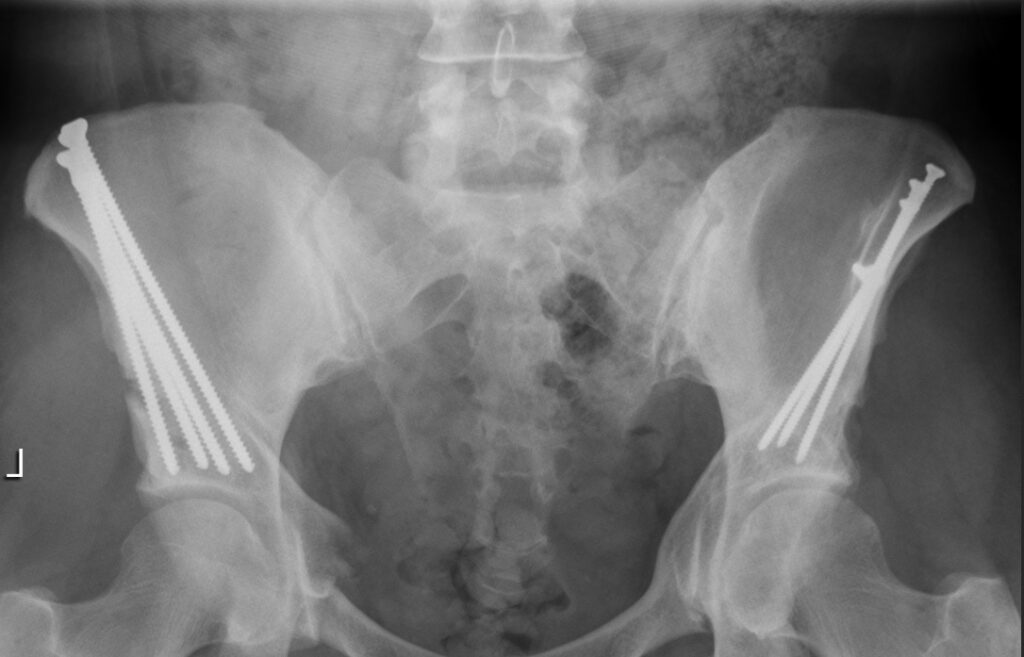

The report at my appointment was positive. After X-rays, they confirmed everything is healing as expected. The physician assistant removed the stitches from my scope incisions and let me know the stitches from the much larger PAO incision would dissolve on their own.